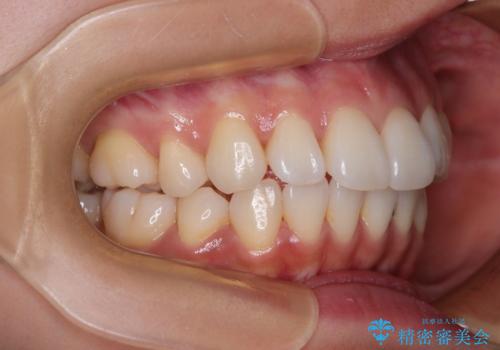

1. 抜歯矯正の軽度後戻りを解消 インビザライン矯正の治療前